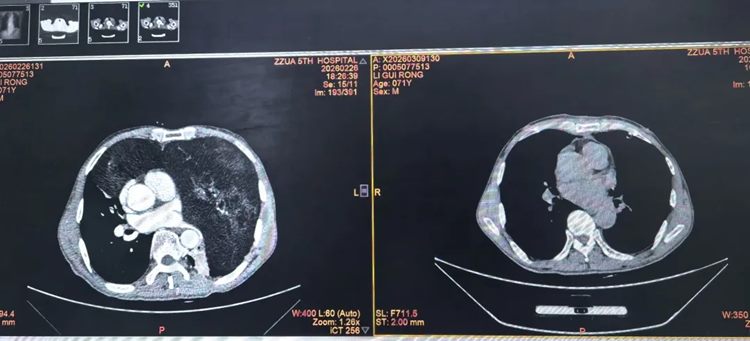

▲ 术前(左侧)与术后(右侧)纵隔窗对比

▲ 术后复查纵隔窗(左侧)与肺窗(右侧)